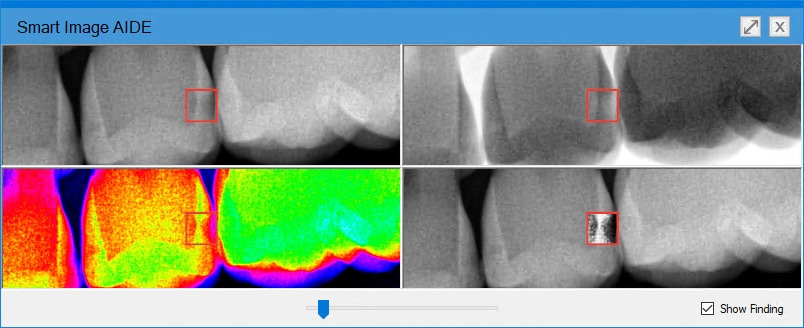

The Smart Image AIDE dialog box appears.

Note: The AIDE view consists of four different versions of the image in a quadrant. In the upper-left, the image is sharpened; in the upper-right, the image is inverted; in the lower-right, the contrast is increased; and in the lower-left, color enhances the image.

6. To remove the AI indicators, clear the Show Finding check box.